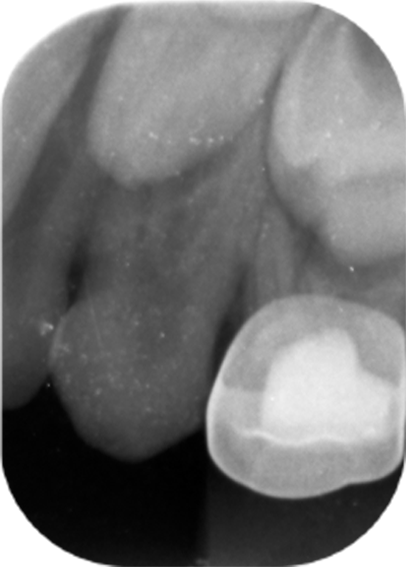

A 6-year-old Saudi male patient referred from one of the Primary Health Care centers in Dammam City to the Pediatric Dental Department at Dammam Medical Complex as a case of uncooperative behavior. The patient’s medical history did not reveal any medical illnesses. Intraoral clinical examination revealed a primary dentition with multiple carious teeth and no soft tissue abnormality was detected. Radiographic intraoral examination confirmed the clinical findings of tooth decays, and interestingly has shown a maxillary canines with two roots (Figures 1 and 2).

Figure 1. Periapical radiograph of the right maxillary primary canine showing a rare bifurcation of the root, consistent with a bi-rooted morphology